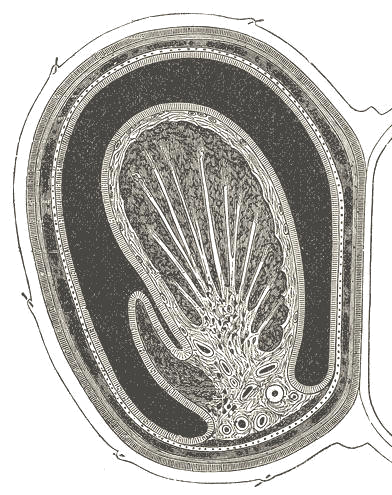

Left testis

Vel / Skin Dartos fassia en spier / Dartos fascia and muscle Buitenste spermatiese fassia / External spermatic fascia Kremaster fassia en spier / Cremasteric fascia and muscle Interne spermatiese fassia / Internal spermatic fascia Pariëtale tunica vaginalis / Parietal tunica vaginalis Visserale tunica vaginalis / Visceral tunica vaginalis Holte van tunica vaginalis / Cavity of tunica vaginalis Lobbe van testis / Lobules of testis Septa van testis / Septa of testis Rete testis Ductus deferens Epididimus / Epididymus Bloedvate / Blood vessels